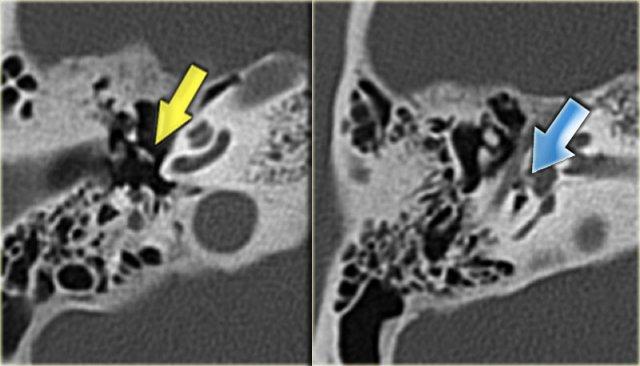

Hình ảnh bên trái của bệnh nhân nam 14 tuổi với điếc tiếp nhận hai bên.

Vôi hóa ống bán khuyên trên bên trái (mũi tên vàng).

Tai phải để so sánh (mũi tên xanh lam).

Hình ảnh mặt phẳng coronal của cùng bệnh nhân trên.